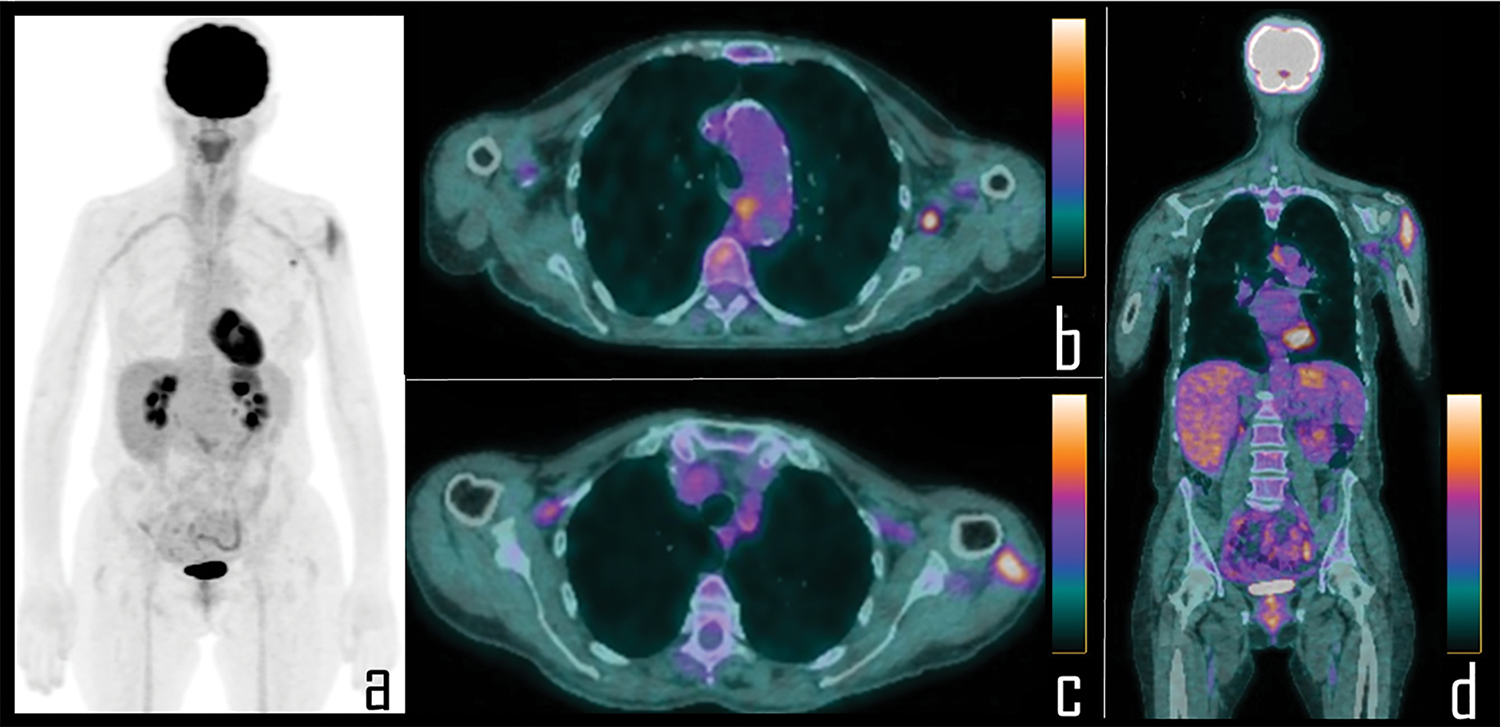

We observed axillary and/or deltoid 2-[18F]FDG uptake, related to COVID-19 vaccine administration, in 89/104 subjects (85%). Among these, 57/89 (64%) had received the first dose of vaccine prior to the PET/CT scan (Fig. 1) while 32/89 (36%) were also administered with the second dose (Fig. 2) of mRNA vaccine (see Table 2).

Figure 2: A 56-year-old female patient underwent 2-[18F]FDG PET/CT during follow up of colon cancer. PET Maximum Intensity Projection (a) was negative for disease relapse but showed focal area of uptake in the left axilla and diffuse tracer uptake in the ipsilateral arm. Axial PET/CT views better display the uptake respectively associated to a single axillary lymph node (b) and the ipsilateral deltoid muscle (c), which was the site of the second COVID-19 vaccine administration, occurred 8 days before the scan. Coronal PET/CT view (d) better displays diffuse uptake in the left deltoid muscle.

Mean time of the PET/CT scan after vaccine administration was 12 days (± 3) for patients submitted to the first vaccine dose and 10 days (± 4) for those patients who had also received the second dose (Fig. 3).

Figure 3: A 65-year-old female patient was examined by means of 2-[18F]FDG PET/CT during follow-up of ovarian cancer. PET Maximum Intensity Projection (a) was negative for disease relapse but showed a focal area of tracer uptake in the left axilla. Patient was previously submitted (14 days before) to second dose of COVID-19 vaccine in the deltoid muscle of left arm. Axial PET/CT view (b, curved arrow) shows the uptake in association with a 0.8 cm wide lymph node, with fatty hilum at correlative low dose axial CT (c, curved arrow). Subsequently, patient underwent whole body contrast enhanced CT, not showing disease relapse but confirming the axillary lymph node in left axilla, with low contrast enhancement (d, curved arrow). Ultrasonography was performed, displaying benign, 0.8 cm wide lymph node with regular shape (e), dominant central hilar flow and peripheral flow at color-doppler (f).